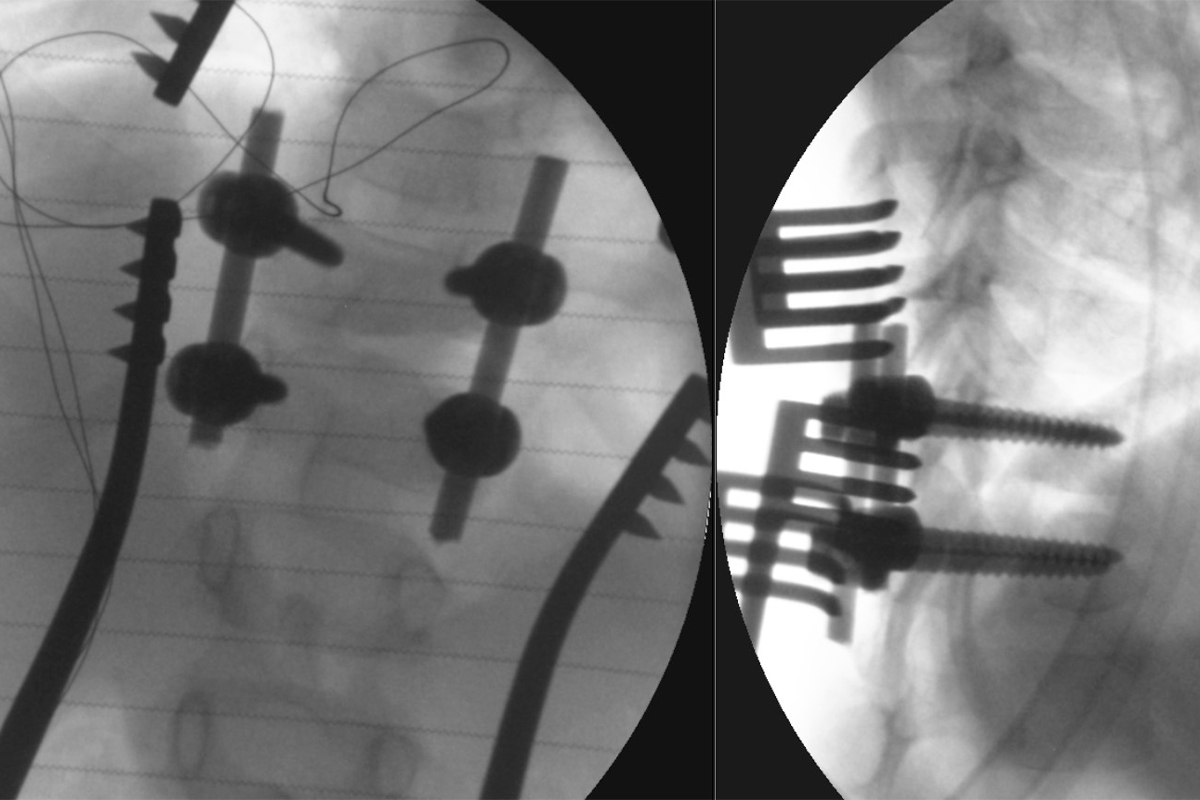

19 февраля совместной белорусско-российской бригадой на базе РНПЦ травматологии и ортопедии была выполнена хирургическая операция ребенку 4 лет с тяжелой врожденной деформацией позвоночника, что стало возможным благодаря реализованной программе Союзного государства «Разработка новых спинальных систем с использованием технологий прототипирования в хирургическом лечении детей с тяжёлыми врождёнными деформациями и повреждениями позвоночника».